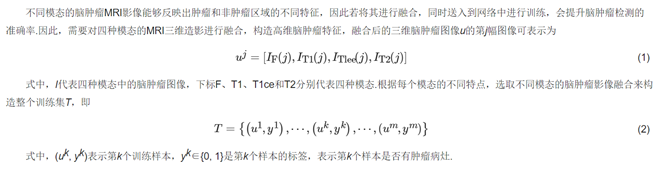

脑肿瘤检测网络:

图 2 脑肿瘤检测网络示意图

整个网络分为收缩路径和扩张路径两个部分:收缩路径的目的为特征提取,由输入层、三维卷积、实例正则化、三维最大池化构成;扩张路径的目的为特征提取和扩大特征图的尺寸,由三维上采样、特征级联以及输出层构成.脑肿瘤检测网络参数设置为:初始化学习率为0.000 1,训练和验证过程的批处理样本数均为1,优化器为Adam,权值初始化方式为Golort_normal,激活函数为ReLU,收缩路径和膨胀路径的网络深度均为5.